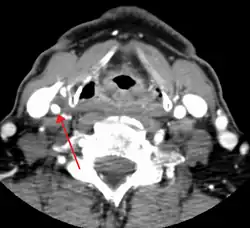

One of several different imaging modalities, such as a computed tomography angiogram (CTA)[18][19][20] or magnetic resonance angiogram (MRA) may be useful. Each imaging modality has its advantages and disadvantages - Magnetic resonance angiography and CT angiography with contrast is contraindicated in patients with chronic kidney disease, catheter angiography has a 0.5% to 1.0% risk of stroke, MI, arterial injury or retroperitoneal bleeding. The investigation chosen will depend on the clinical question and the imaging expertise, experience and equipment available.[21]

Based on the NASCET (The North American Symptomatic Carotid Endarterectomy Trial) criteria, the degree of carotid stenosis is defined as:[22]

- percent stenosis = ( 1 − ( minimum diameter within stenosis) / ( poststenotic diameter ) ) × 100%.